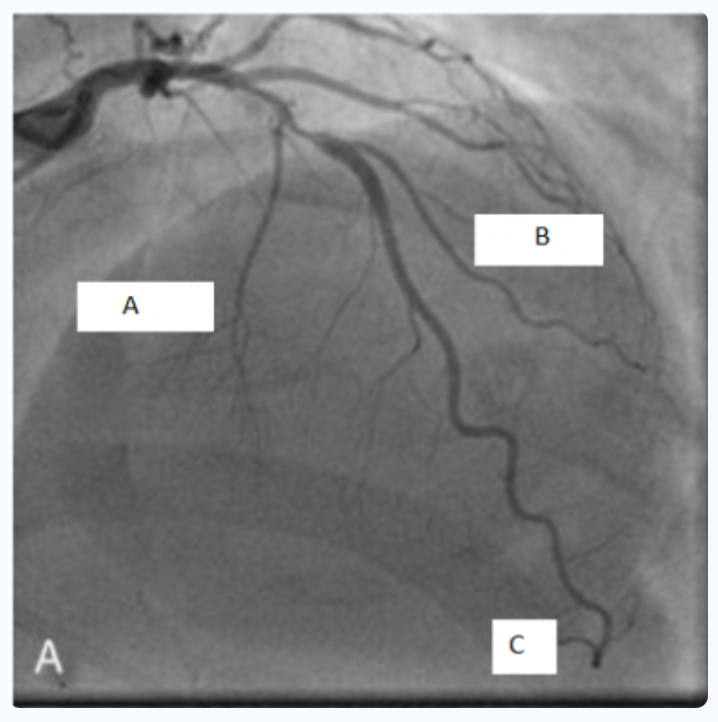

A propos de cet examen : (cf photo)

A B